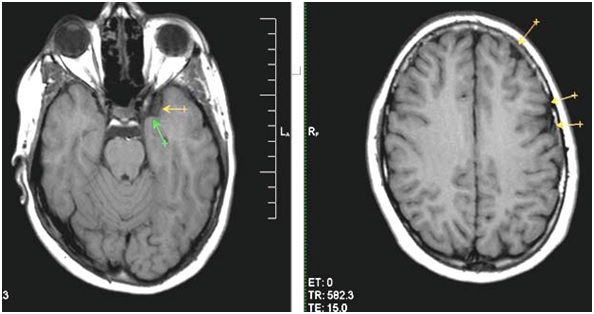

Для постановки диагноза внутричерепной гипотензии необходимо пройти тщательное обследование. Отсутствие в анамнезе недавних травм головы и вмешательств с нарушением целостности мозговых оболочек осложняет диагностический поиск. По результатам МРТ можно заподозрить снижение внутричерепного давления. Это характеризуется следующими признаками:

- утолщение мозговых оболочек;

- оболочки хорошо контрастируются;

- миндалины мозжечка смещены книзу;

- в субдуральном пространстве скапливается жидкость;

- гипофиз увеличен в размере (см. Аденома гипофиза);

- расширение субдуральных вен.